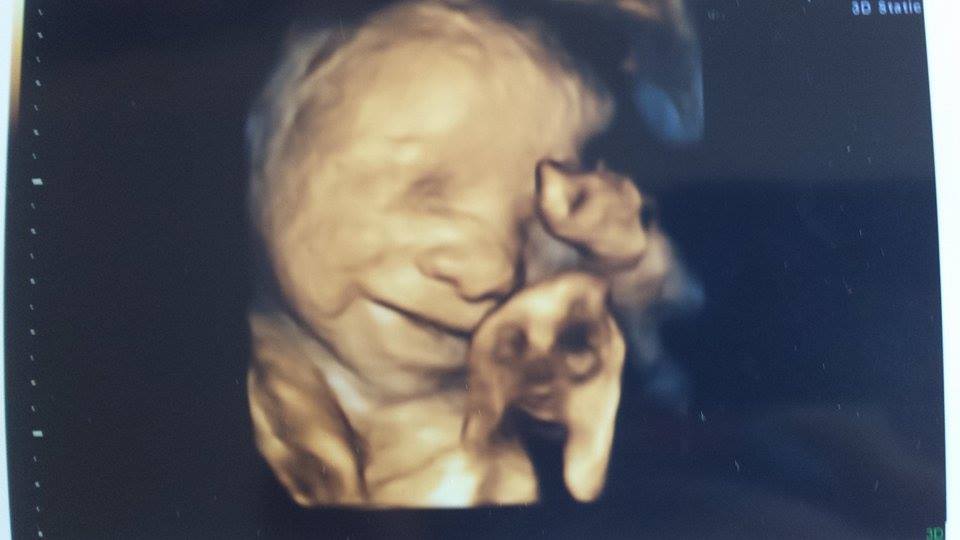

4D scan Published 02/11/2014 at 960 × 540 in Baby Love Recognisable Like this:Like Loading... Share this on:FacebookTwitterLinkedInPinterestMoreRedditEmailTumblrLike this:Like Loading...